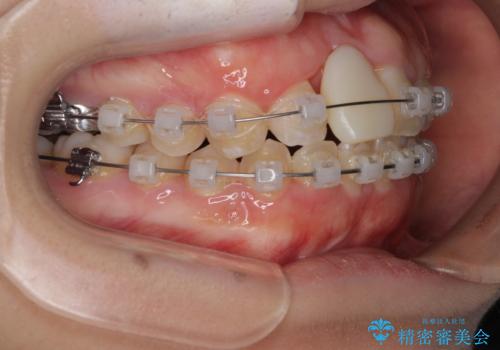

- 矯正装置

- クリアブラケット

- 治療期間

- 2年1ヶ月

ぶつけてしまった歯は保存が困難な状況であったので抜歯をし、ワイヤー矯正により歯列を整えつつ前歯の突出感を解消することとしました。